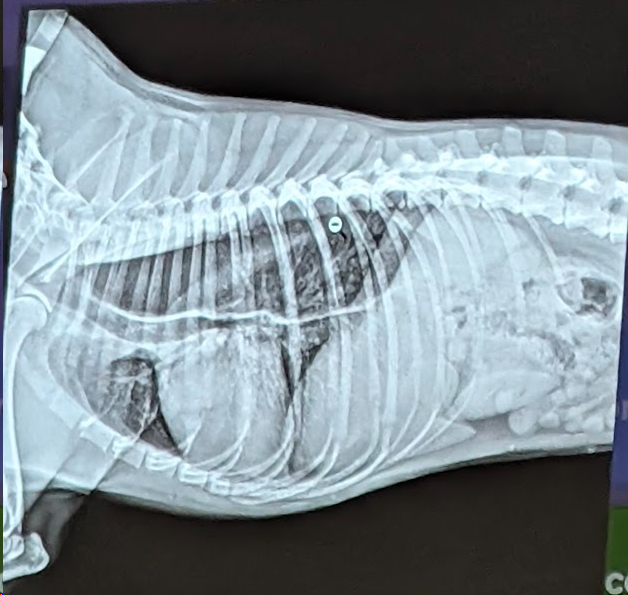

4) Una respuesta correcta

- Enfisema cutaneo (Aire por debajo de la piel)

- Neumomediastino (Aire en el mediastino craneal sobre todo, se ven los vasos demasiado)